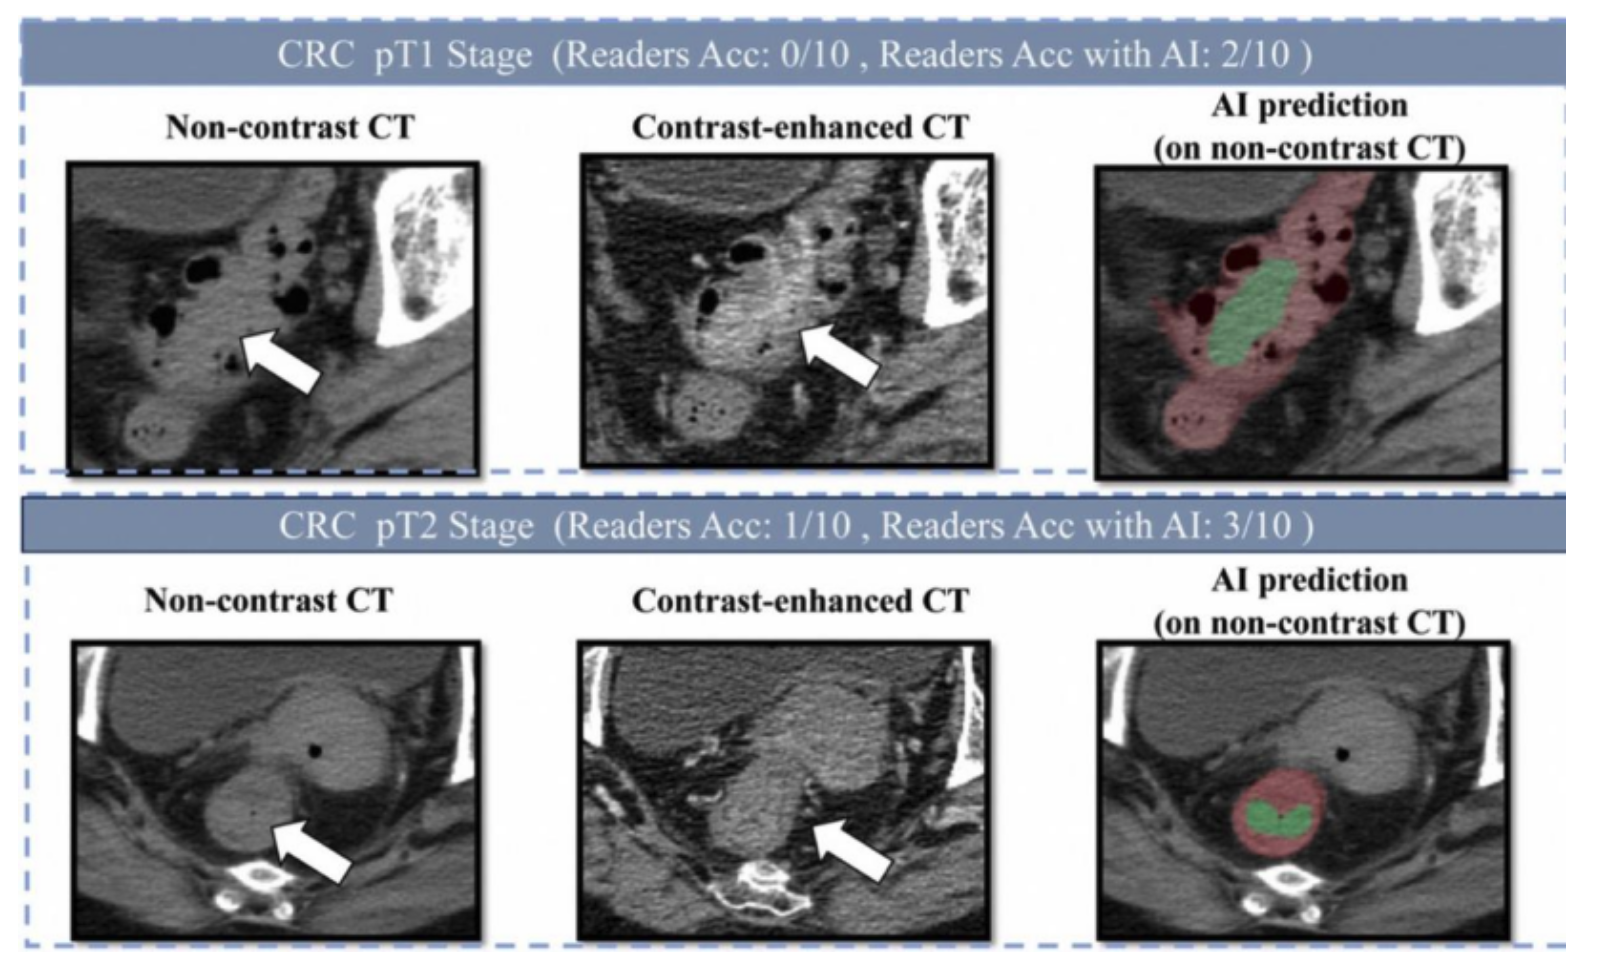

肠癌病灶在平扫CT、增强CT和AI画面上的表现

研究团队发表在欧洲肿瘤内科学会官方期刊《肿瘤学年鉴》(Annals of Oncology,影响因子65.4)上的论文显示,DAMO COCA模型的敏感性(即防止漏诊的能力)达到86.6%,特异性更达到99.8%,即误诊率仅有0.2%。与10名不同年资的影像科医生相比,DAMO COCA模型的敏感性显著高出20.4%,在乙状结肠、直肠等易漏部位上的表现尤为突出。而在AI辅助下,医生的敏感性和特异性可分别提高14.5%和3.1%,有效减少临床漏诊。